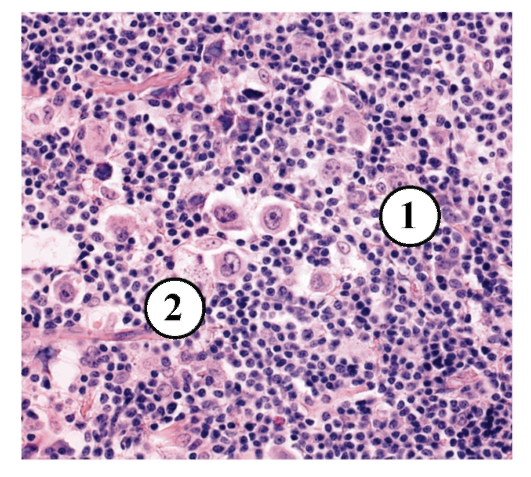

Микропрепараты: Лимфогранулематоз и Нодулярный Склероз

Раздел: Секреты мастерства